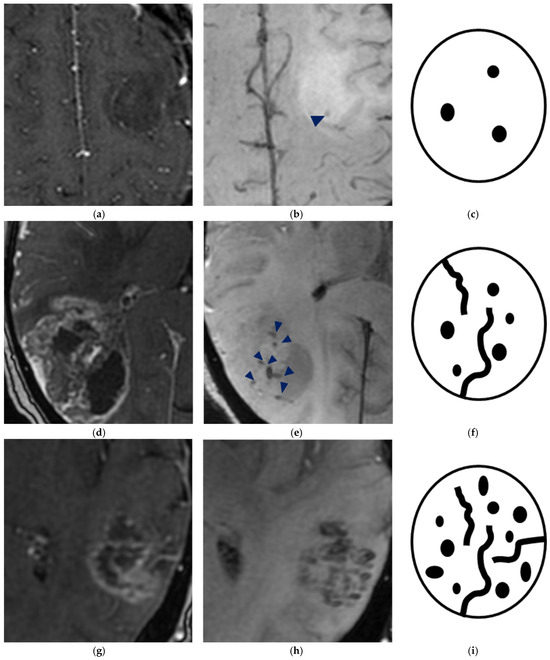

- Park, M.J.; Kim, H.S.; Jahng, G.H.; Ryu, C.W.; Park, S.M.; Kim, S.Y. Semiquantitative assessment of intratumoral susceptibility signals using non-contrast-enhanced high-field high-resolution susceptibility-weighted imaging in patients with gliomas: Comparison with MR perfusion imaging. AJNR Am. J. Neuroradiol. 2009, 30, 1402–1408. [Google Scholar] [CrossRef]